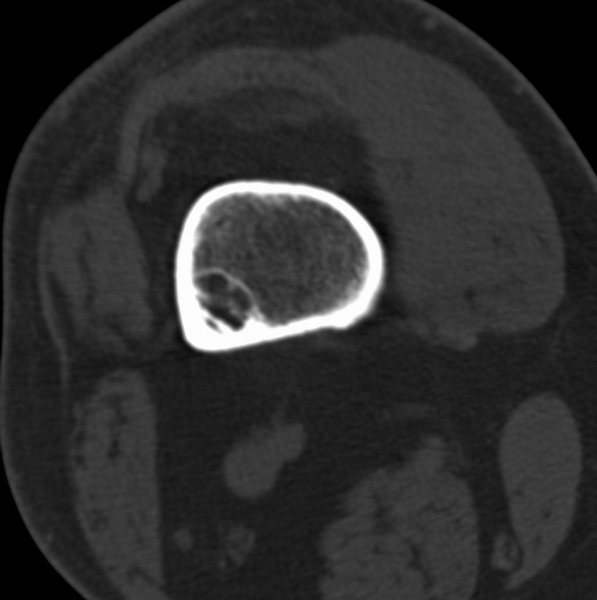

标题: CT21959:骨肿瘤请会诊。

右侧膝关节疼痛一月

男、48

股骨下段、胫骨上段。

股骨干骺端病变考虑非骨化性纤维瘤。

1、股骨干骺端病变考虑干骺端纤维性皮质缺损愈后(非骨化性纤维瘤)改变,胫骨近端内生骨瘤;

2、骨关节炎,骨质增生,股骨外侧髁退变性囊肿(关节面软骨下囊肿);